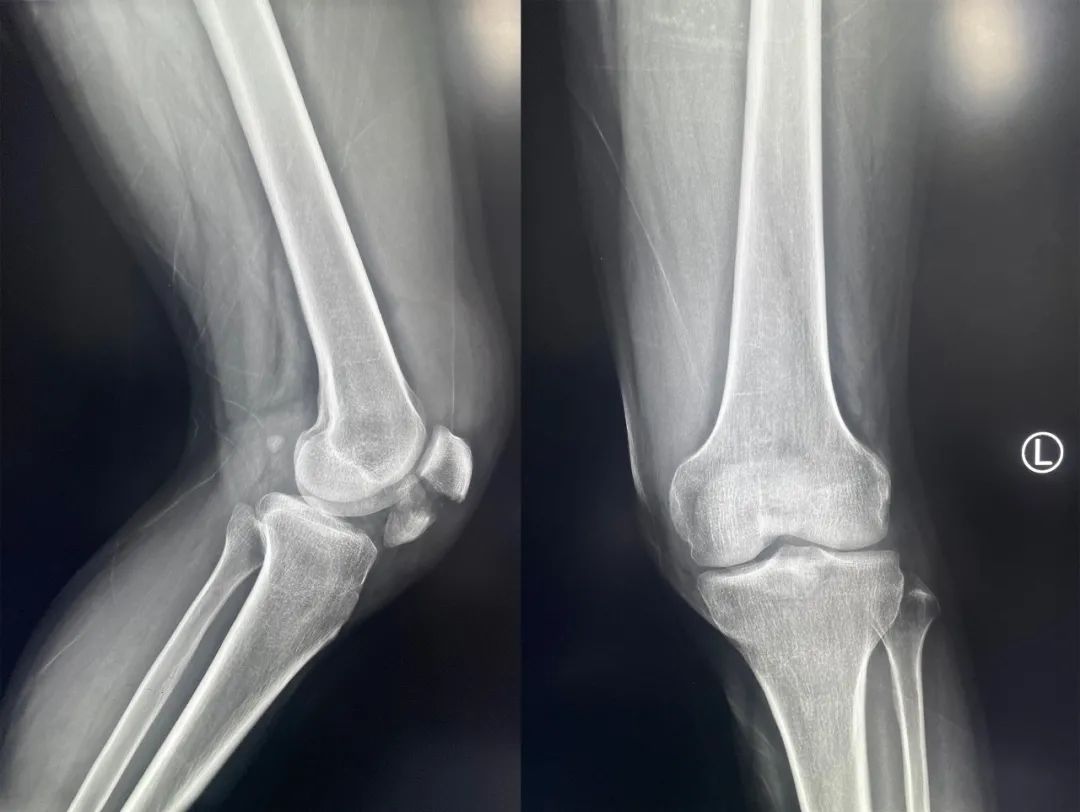

髌骨骨折只占全身骨折的 1%,治疗方式的选择和并发症的防治尤其要注意,急诊来了髌骨骨折患者,你怎么处理?髌骨是人体最大的籽骨,位于膝关节伸膝装置内。解剖特点包括近端宽大的基底和关节外的远侧尖端,前面位于关节外,后面为关节面。股直肌和股中间肌止于髌骨基底部,股内侧肌和股外侧肌止于髌骨的两侧。髌腱起于髌骨尖端,止于胫骨结节。髌骨骨折约占所有骨折的 1%,主要由直接暴力造成,如跌倒时跪地或膝关节屈曲时受到打击。典型的体征包括关节肿胀、压痛、伸膝功能部分或完全丧失。除以主诉和典型体征外,膝关节 X 线片也是必不可少的一项辅助检查,以膝关节正侧位 X 线片最常见,如果怀疑纵向骨折,膝关节屈曲 45° 时髌骨 30° 切位片可以辅助诊断。对于骨折不愈合、畸形愈合所致的关节面不平整以及髌股关节对应关系不良可采用 CT 检查。MRI 有助于诊断软骨缺损和损伤。34-B 型(部分关节内骨折,伸膝装置完整,如纵行骨折)髌骨下极骨折袢钢板结合克氏针、张力带固定 图源:作者提供